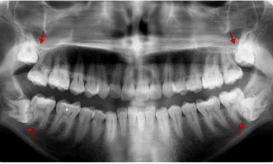

Το ξέρατε; Περισσότεροι από ένας στους 12 ανθρώπους γεννιούνται με λιγότερα δόντια από το φυσιολογικό, με συνέπεια τα δόντια...